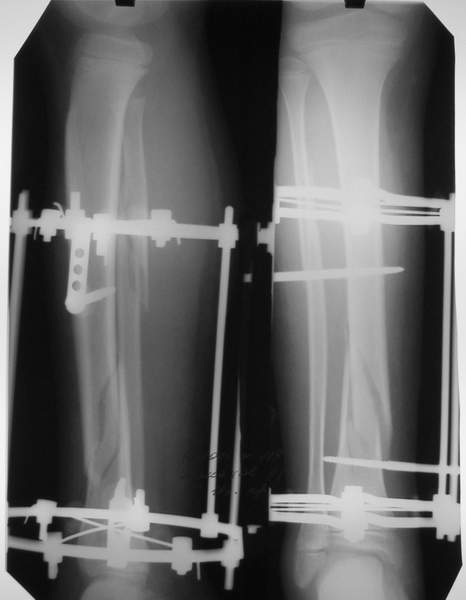

Под рукой прилагаемый пример. Как видите, "стриптиз-аппарат" (шутка проф. З.К.Башурова): 3 кольца-2 кольца-2 полукольца. В случае, который представил Евгений, характер повреждения позволил бы сразу использовать аппарат на основе 2 колец; в крайнем случае прокс. опора м.б. демонтирована сразу после репозиции.

Подробная информация о методе Модульной Трансформации чрескостных аппаратов представлена в проаннонсированной недавно РосНИИТО монографии по чрескостному остеосинтезу; надеюсь выйдет в свет в апреле (не реклама :-) ).

В аттачте № 3 - один из примеров полукольцевого аппарат...

Это уже я баловался.

Итог? Работы больше (по времени и

интраоп "подгонке"), срастается также, а особого преимущества по сравнению с

"чиста" кольцевым (вес, удобство ношения и пр.) - я, по крайней мере,

не нашел.

Теперь не балуюсь.

Может быть зря?